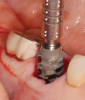

Recognizing that achieving primary stability in extraction sites is more challenging than in healed ones, the use of tapered implants may be considered to achieve better primary stability for immediate implant placement. Kan and colleagues reported decreased rotational instability with tapered implants in immediate placement protocols.9 Utilizing an implant with well-defined threads that improve lateral bone engagement may improve stability (Figure 1 through Figure 4). Conceptually, it makes sense to use tapered implants or those with threads that cut and condense bone; however, there is little evidence in the literature supporting superior primary stability based on implant design.10 Although implant design may offer advantages, clinicians should focus more on site preparation and final drill selection as the keys to achieving adequate primary stability.

(2.) This series of clinical images illustrates the use of an implant with well-defi ned

threads that improve lateral bone engagement. In a multirooted extraction socket where there are large voids, this can help to achieve initial implant stability.

Figure 2